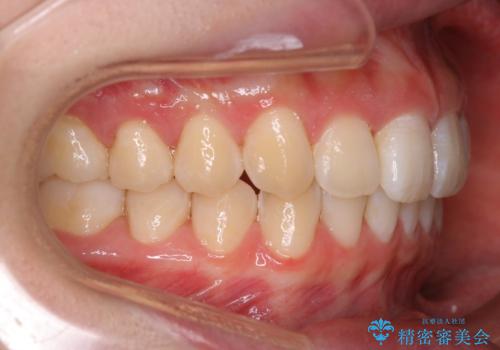

- 初診時、前歯のガタつきを主訴にご来院されました。

精密検査の結果奥歯の噛み合わせのズレからくる前歯のガタつきであることが分かり、患者様と相談した結果、全体をしっかりと治療することをご選択なさったので奥歯から動かして噛み合わせと見た目の両方を治す治療プランとなりました。

下顎の歯は幸いガタつきが少なかったため、下顎を基準とし構成する方針としました。

初診時の写真では一見噛み合わせには問題がないように見えても、実際に精密な検査を行うと改善すべき点が見つかる場合も多くあります。

当院では、矯正治療は見た目の改善が主目的ではなく機能面を改善し自然に長持ちする口腔内環境を整えることに重きを置く必要があると考えます。